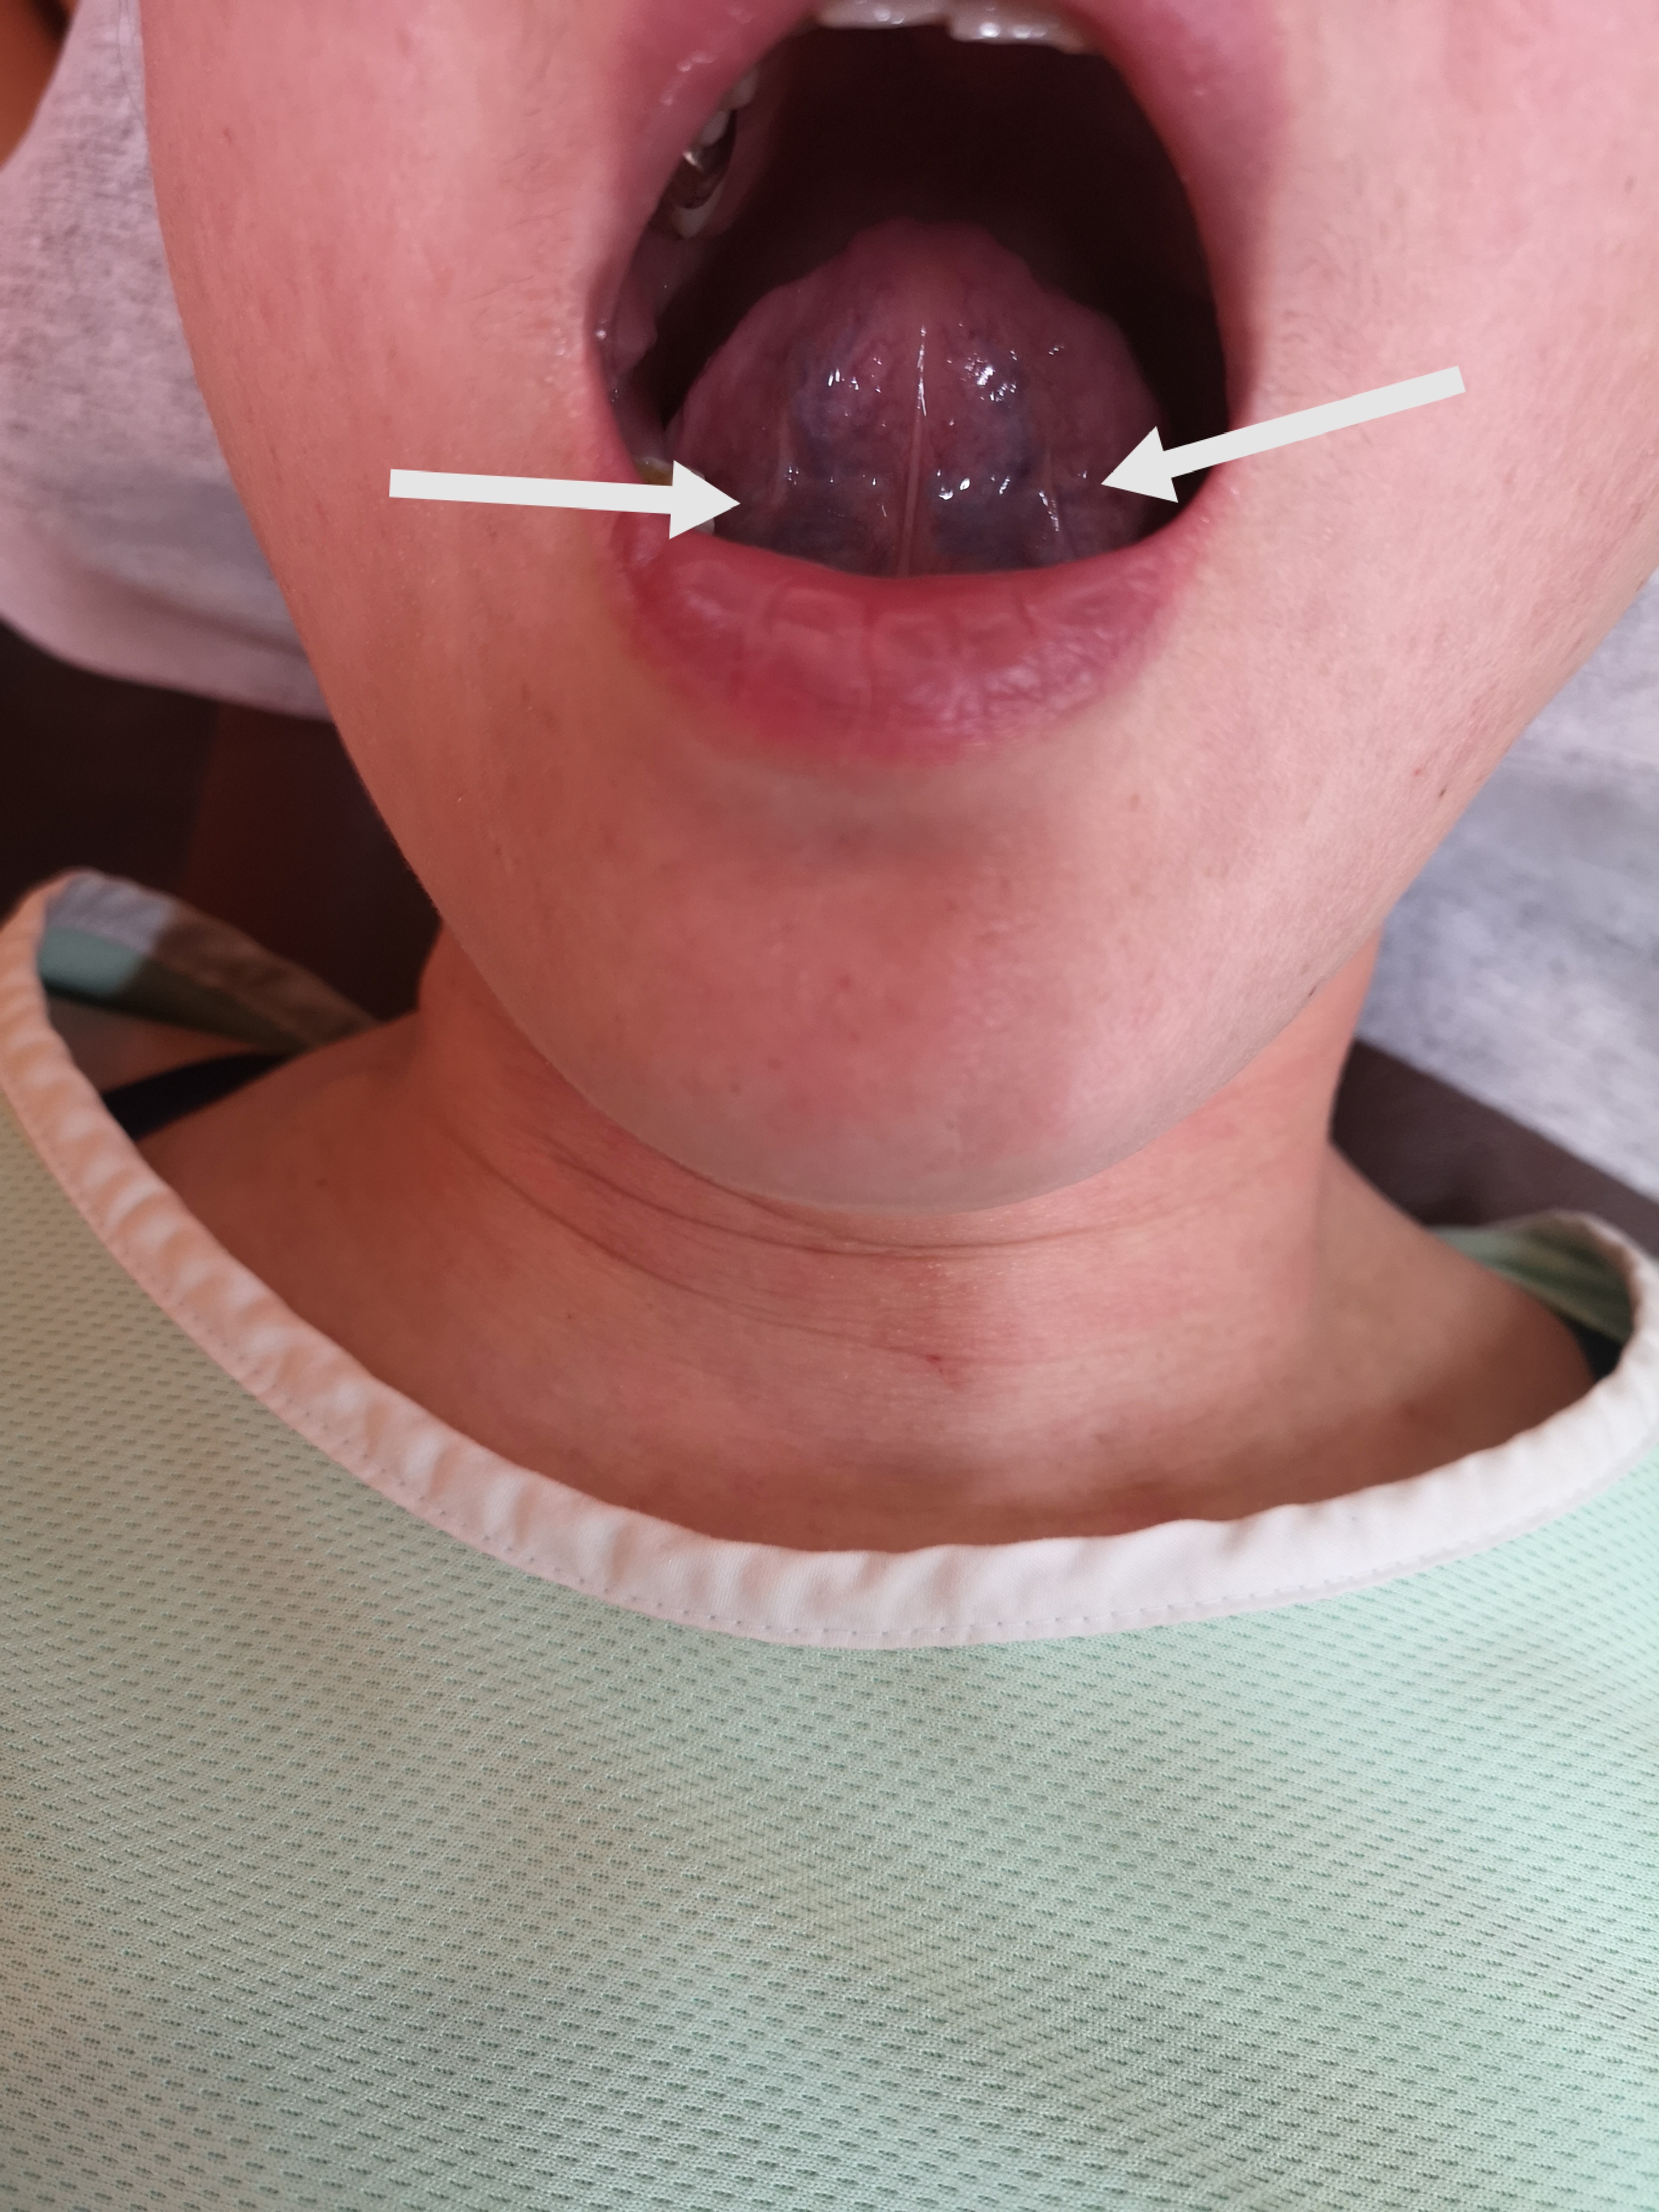

初診時の舌の状態がこちら

舌全体が赤黒く静脈の怒張が顕著です。からだのあちこちが痛くなるのは「肝風」と言いますが

、血瘀、陰虚などが関連します。常に交感神経が優位になり脳が興奮状態であると痛みが増幅されます。